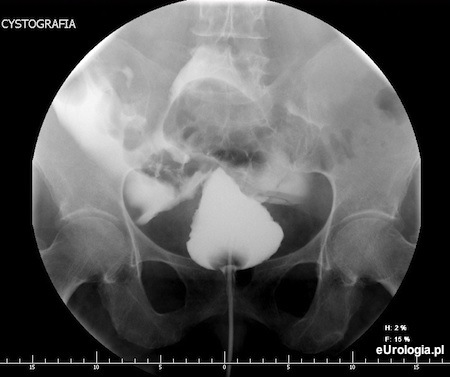

Perforacja pęcherza moczowego czyli przebicie jego ściany. Do perforacji pęcherza moczowego dochodzi najczęściej w wyniku urazów podbrzusza lub w czasie endoskopowych operacji guzów pęcherza moczowego. Perforację pęcherza rozpoznaje się wykonując cystografię.

Fot. Perforacja pęcherza moczowego - cystografia.